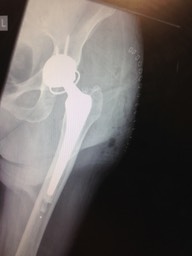

Revision hip replacement - pictures

IMG_0538

1